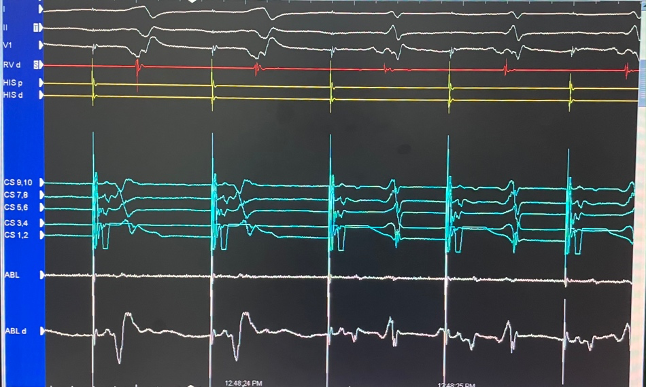

Tiến hành map vùng sau vách bên phải vòng van 3 lá ghi nhận điện thế nhĩ thất hoà vào nhau tương tự sau vách bên trái. Tiến hành cắt đốt vị trí này thì chấm dứt đường phụ nhưng sau đó tái phát lại. Tiến hành thăm dò vùng vị trí thượng mạc trong lỗ tĩnh mạch vành hướng về bên trái ghi nhận điện thế nhĩ thất hoà vào nhau làm 1, tiến hành cắt đốt vị trí này thì chấm dứt hoàn toàn đường dẫn truyền phụ này. Bệnh nhân khôi phục nhịp xoang dẫn truyền hoàn toàn qua nút nhĩ thất thông thường.

Hình: vị trí cắt đốt thành công trong xoang vành bằng catheter năng lượng cao và hình ảnh xoang vành.

Cắt đốt thành công mất sóng delta từ nhịp tim thứ 3, QRS hẹp lại.